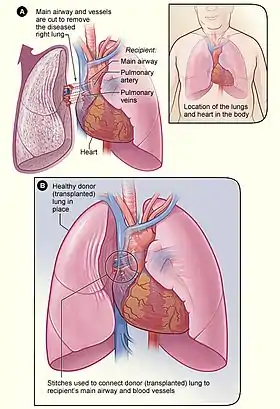

Pulmonary veno-occlusive disease (PVOD) is a rare form of pulmonary hypertension caused by progressive blockage of the small veins in the lungs.[2] The blockage leads to high blood pressures in the arteries of the lungs, which, in turn, leads to heart failure. The disease is progressive and fatal, with median survival of about 2 years from the time of diagnosis to death.[3] The definitive therapy is lung transplantation.[4]

The definitive therapy is lung transplantation, though transplant rejection is always a possibility, in this measures must be taken in terms of appropriate treatment and medication.[11][12]